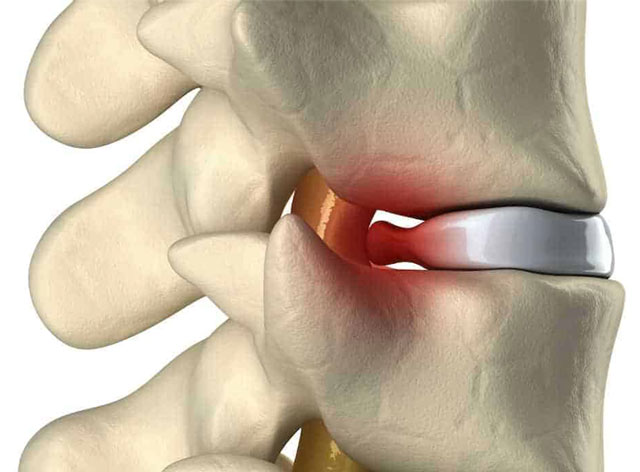

Tratamento de Hérnia de Disco

Se você já tem um diagnostico de Hérnia de disco ou sente dores crônicas ou agudas na coluna, entre em contato, nossa maca de flexo tração é a melhor ferramenta para o seu tratamento.